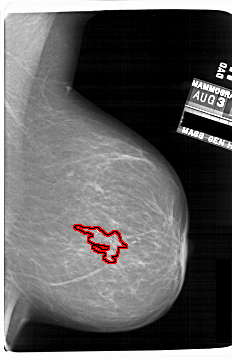

A_1690_1.RIGHT_CC

FILE: A_1690_1.RIGHT_CC.OVERLAY

TOTAL_ABNORMALITIES 1

ABNORMALITY 1

LESION_TYPE CALCIFICATION TYPE AMORPHOUS DISTRIBUTION CLUSTERED

ASSESSMENT 4

SUBTLETY 4

PATHOLOGY BENIGN

TOTAL_OUTLINES 1

BOUNDARY